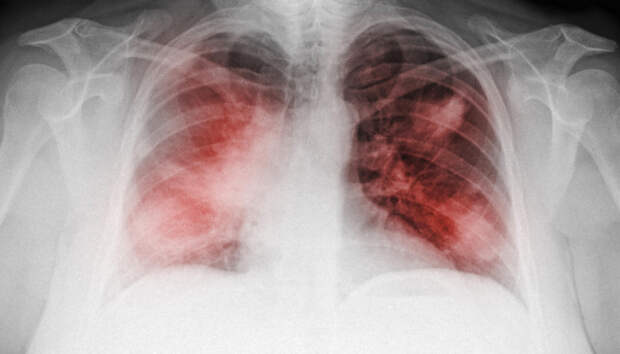

За минувшие сутки в блечебные учреждения с воспалением легких попало двенадцать человек Двенадцать человек за сутки госпитализированы с внебольничной пневмонией в Карелии, сообщает оперативный штаб по борьбе с распространением COVID-19 в Карелии. Летальных исходов от внебольничной пневмонии не зарегистрировано.

Начиная с 1 апреля, с внебольничной пневмонией госпитализированы 1285 пациентов, 76 человек умерли (с учетом пациентов, […]